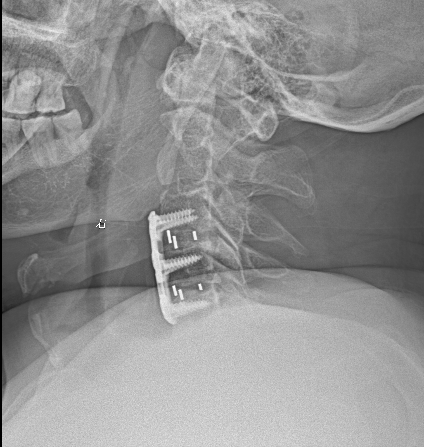

2.手术的目的是“减压”:手术如同为被堵的“高速公路”进行“拓宽清障”。医生会通过微创或开放手术,移除压迫脊髓的椎间盘、骨赘或肥厚的韧带,为脊髓松绑,恢复其赖以生存的空间和血供。

3.阻止恶化,争取恢复:手术的首要目标是阻止病情进一步恶化,防止患者走向瘫痪。其次,是为已经受损的脊髓创造恢复的条件。越早手术,脊髓受压时间越短,神经功能恢复的可能性就越大。张大爷虽然拖延了一段时间,但现在手术,依然是为了保住他未来的行走能力和生活自理能力。